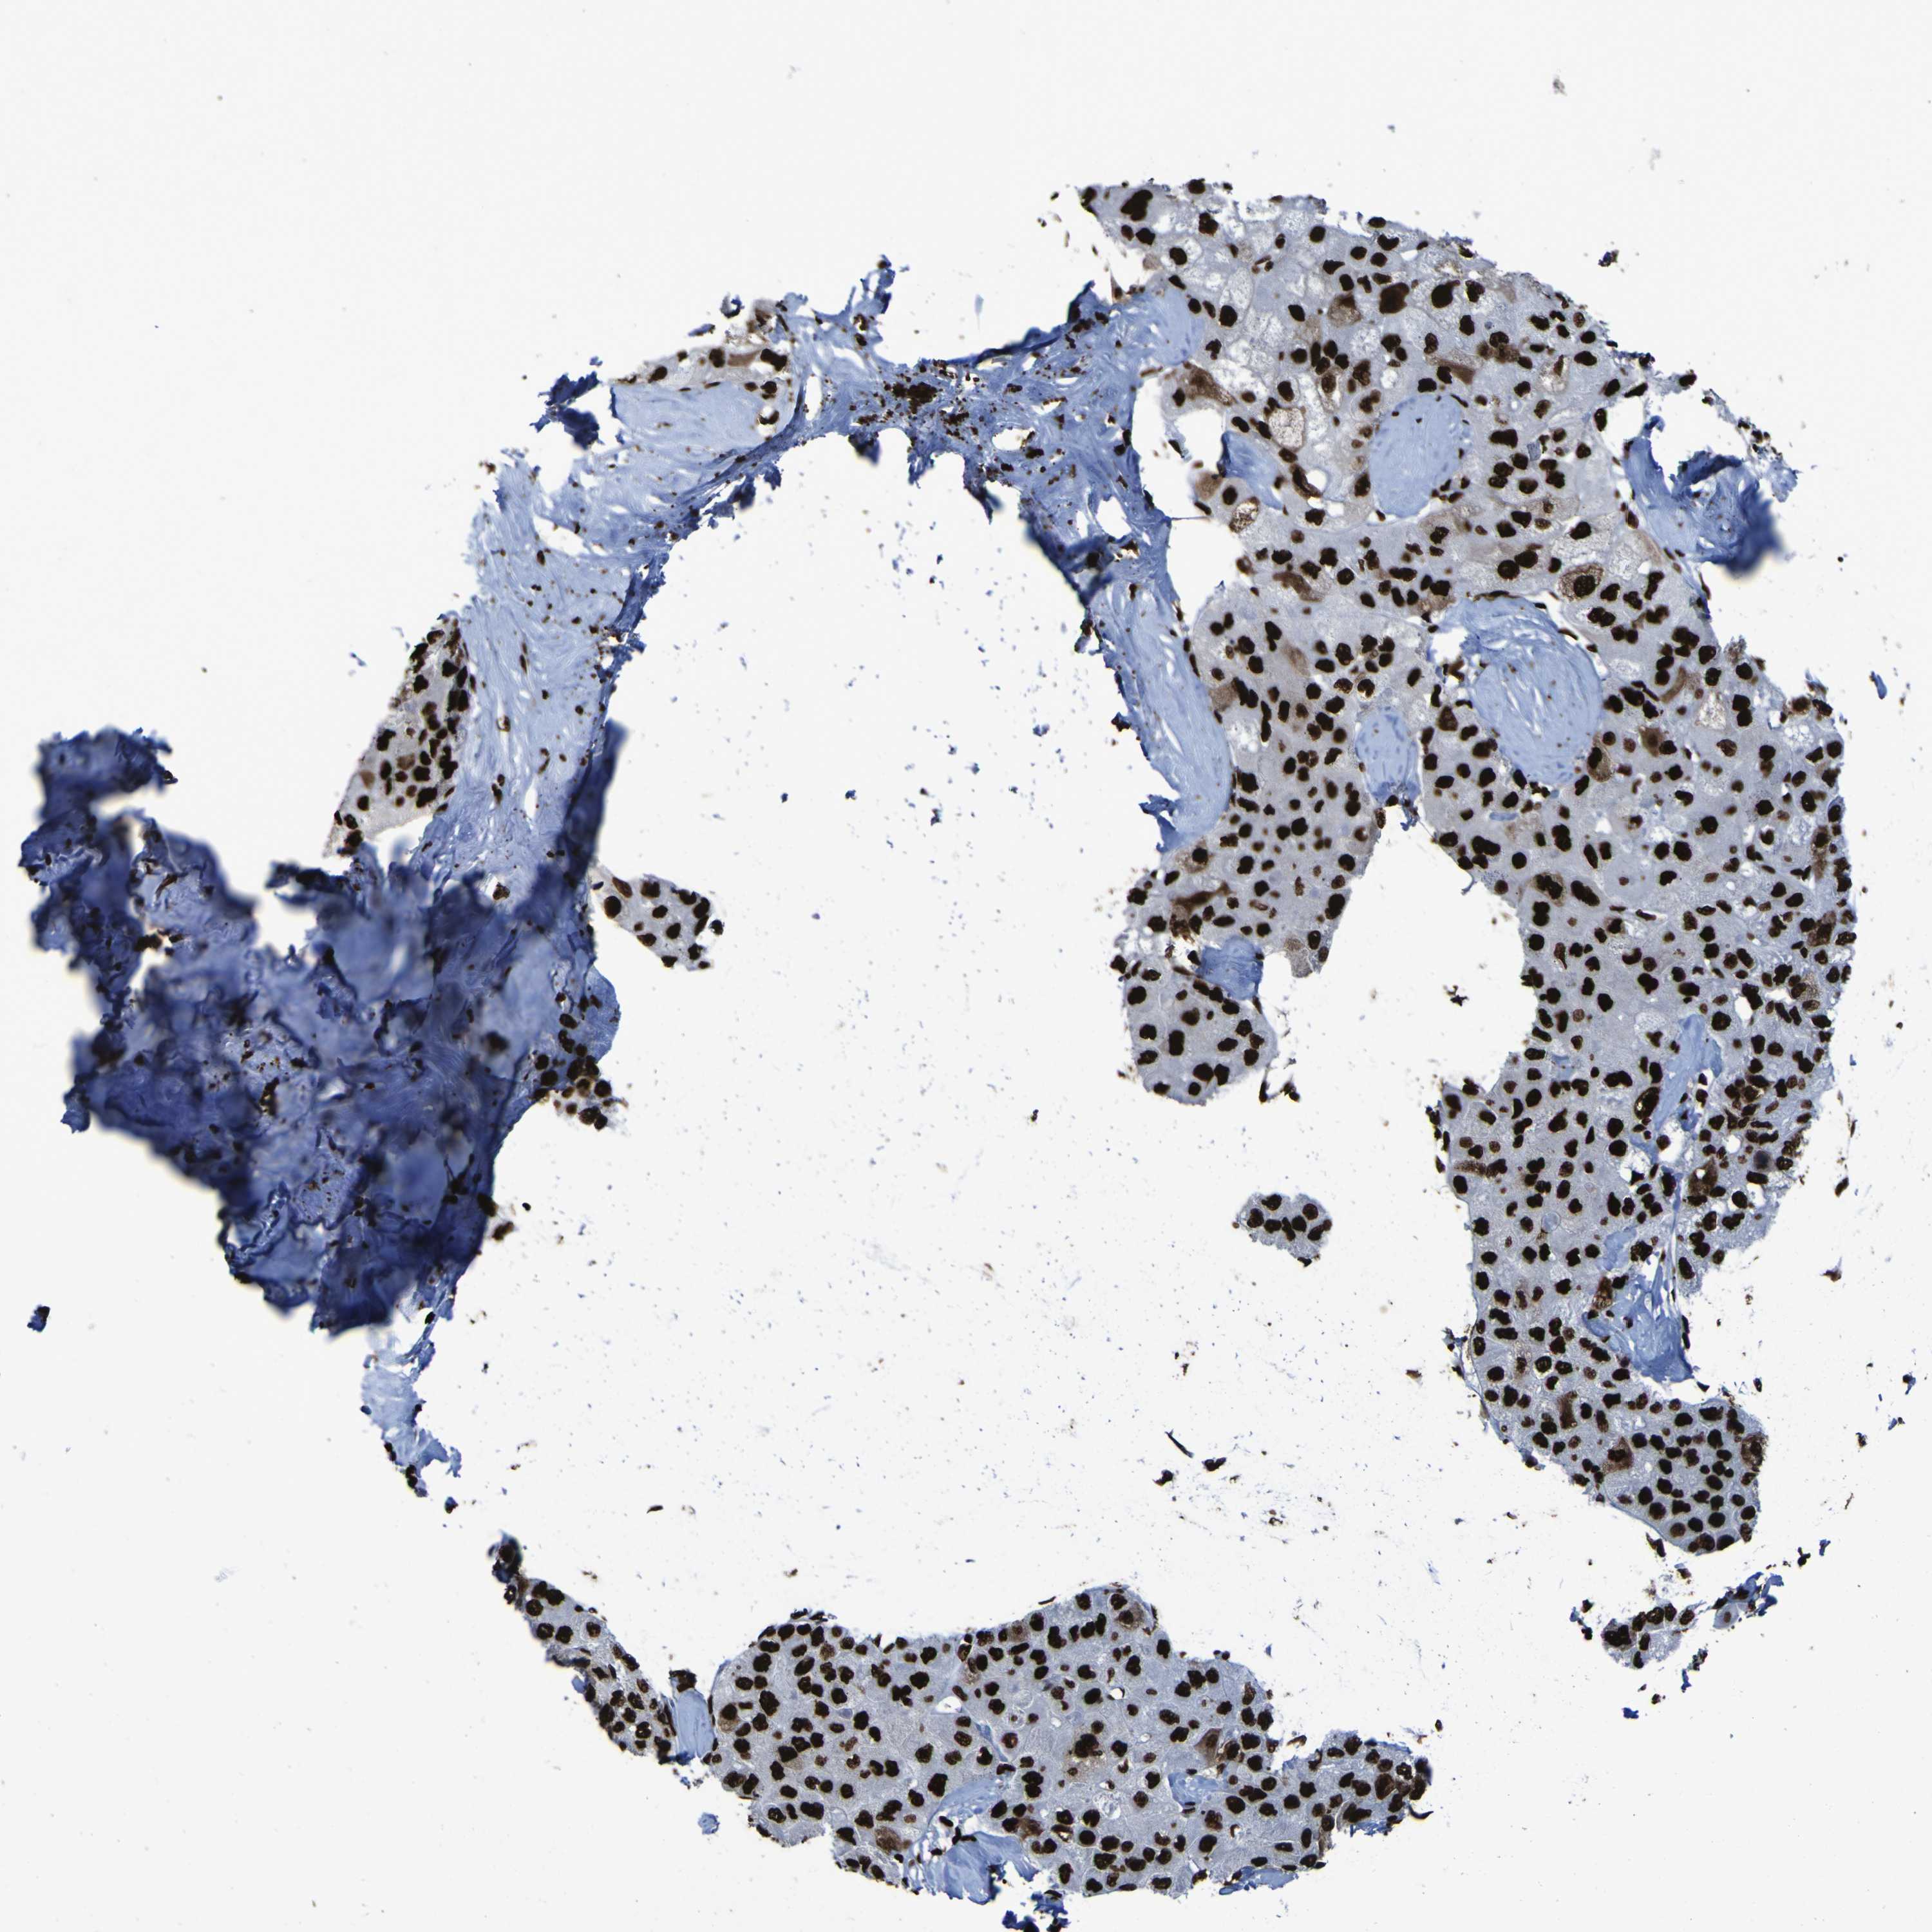

LIVER CANCER - Protein expressioni

A mouse-over function shows sample information and annotation data. Click on an image to view it in a full screen mode. Samples can be filtered based on level of antibody staining by selecting one or several of the following categories: high, medium, low and not detected. The assay and annotation is described here.

Antibody stainingi

Antibody staining in the annotated cell types in the current human tissue is reported as not detected, low, medium, or high, based on conventional immunohistochemistry profiling in selected tissues. This score is based on the combination of the staining intensity and fraction of stained cells.

Each image is clickable and will lead to virtual microscopy that enables deeper exploration of all samples and also displays staining intensity scores, fraction scores and subcellular localization as well as patient and tissue information for each sample.

Antibody HPA011384

Antibody CAB012983

Staining

High

Medium

Low

Not detected

Intensity

Strong

Moderate

Weak

Negative

Quantity

>75%

75%-25%

<25%

None

Location

Nuclear

Cytoplasmic/membranous

Cytoplasmic/membranous,nuclear

Cholangiocarcinoma

Carcinoma, Hepatocellular, NOS